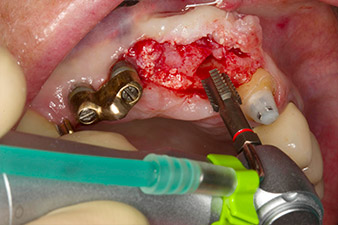

Motorized placement of the implant

Fig. 4: Motorized placement of the implant with the WS-75 L contra-angle handpiece at a ratio of 20:1 (programme P5).